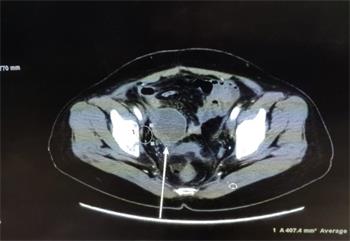

【明慧网二零二三年三月二十三日】二零一八年十月,我的表姑从美国回来就医,她患肝癌十余年,期间多次转移都通过手术切除得以缓解,但这次检查结果很悲观(见图1),是多个脏器的转移,在医院看了肿瘤外科、妇科、胃肠外科、泌尿外科等,各外科专家们均无良策!无奈之下接受了肿瘤内科主任建议的以减轻疼痛为目的的姑息性放疗。

'图1'

图1

在此情况下,我告诉了她大法被迫害的真相,帮她做了三:退.,并告诉她多念“法轮大法好,真善忍好”。就这样,她开始每天念诵九字真言,一天大约四十五分钟(分次完成)。刚开始时,她头脑中的干扰比较严重,我帮她发正念清除后,她可以比较安静的念诵真言。经过近两个月时间,她的症状大为改善,同时也完成一个疗程的放疗。

之后她回到美国,约半个月后她在国外开始复查,她做了CT、超声、磁共振、PET-CT,所有的检查指示肿瘤病灶完全消失了,她非常的震惊,对我说,她见证奇迹了,她一定要坚持念下去。同时她的美国医生和中国医生都对她的治疗效果表示不可思议,这是她度过的第一个死劫。

结果到二零二零年四月的一天,她突感下腹部剧痛,人也无法站立,家人打120送急诊,经超声检查认为是转移瘤,后又行PET-CT检查,报告显示盆腔有一4.9cmx7.3cm的巨大肿块,同样考虑为转移瘤,外科医生收到报告后表示无法手术了!

更为惊奇的是,医生在做CT增强扫描时发现肿瘤可能出现大面积的坏死(见图2,箭头所指肿瘤的阴影部份),后来对肿瘤进行了穿刺,病理报告证实了,肿瘤中间部份变成了坏死组织和炎症细胞(见图3),而这个肿瘤的表面仍然是肝癌细胞(后补充免疫组化报告)。

'图2'

图2